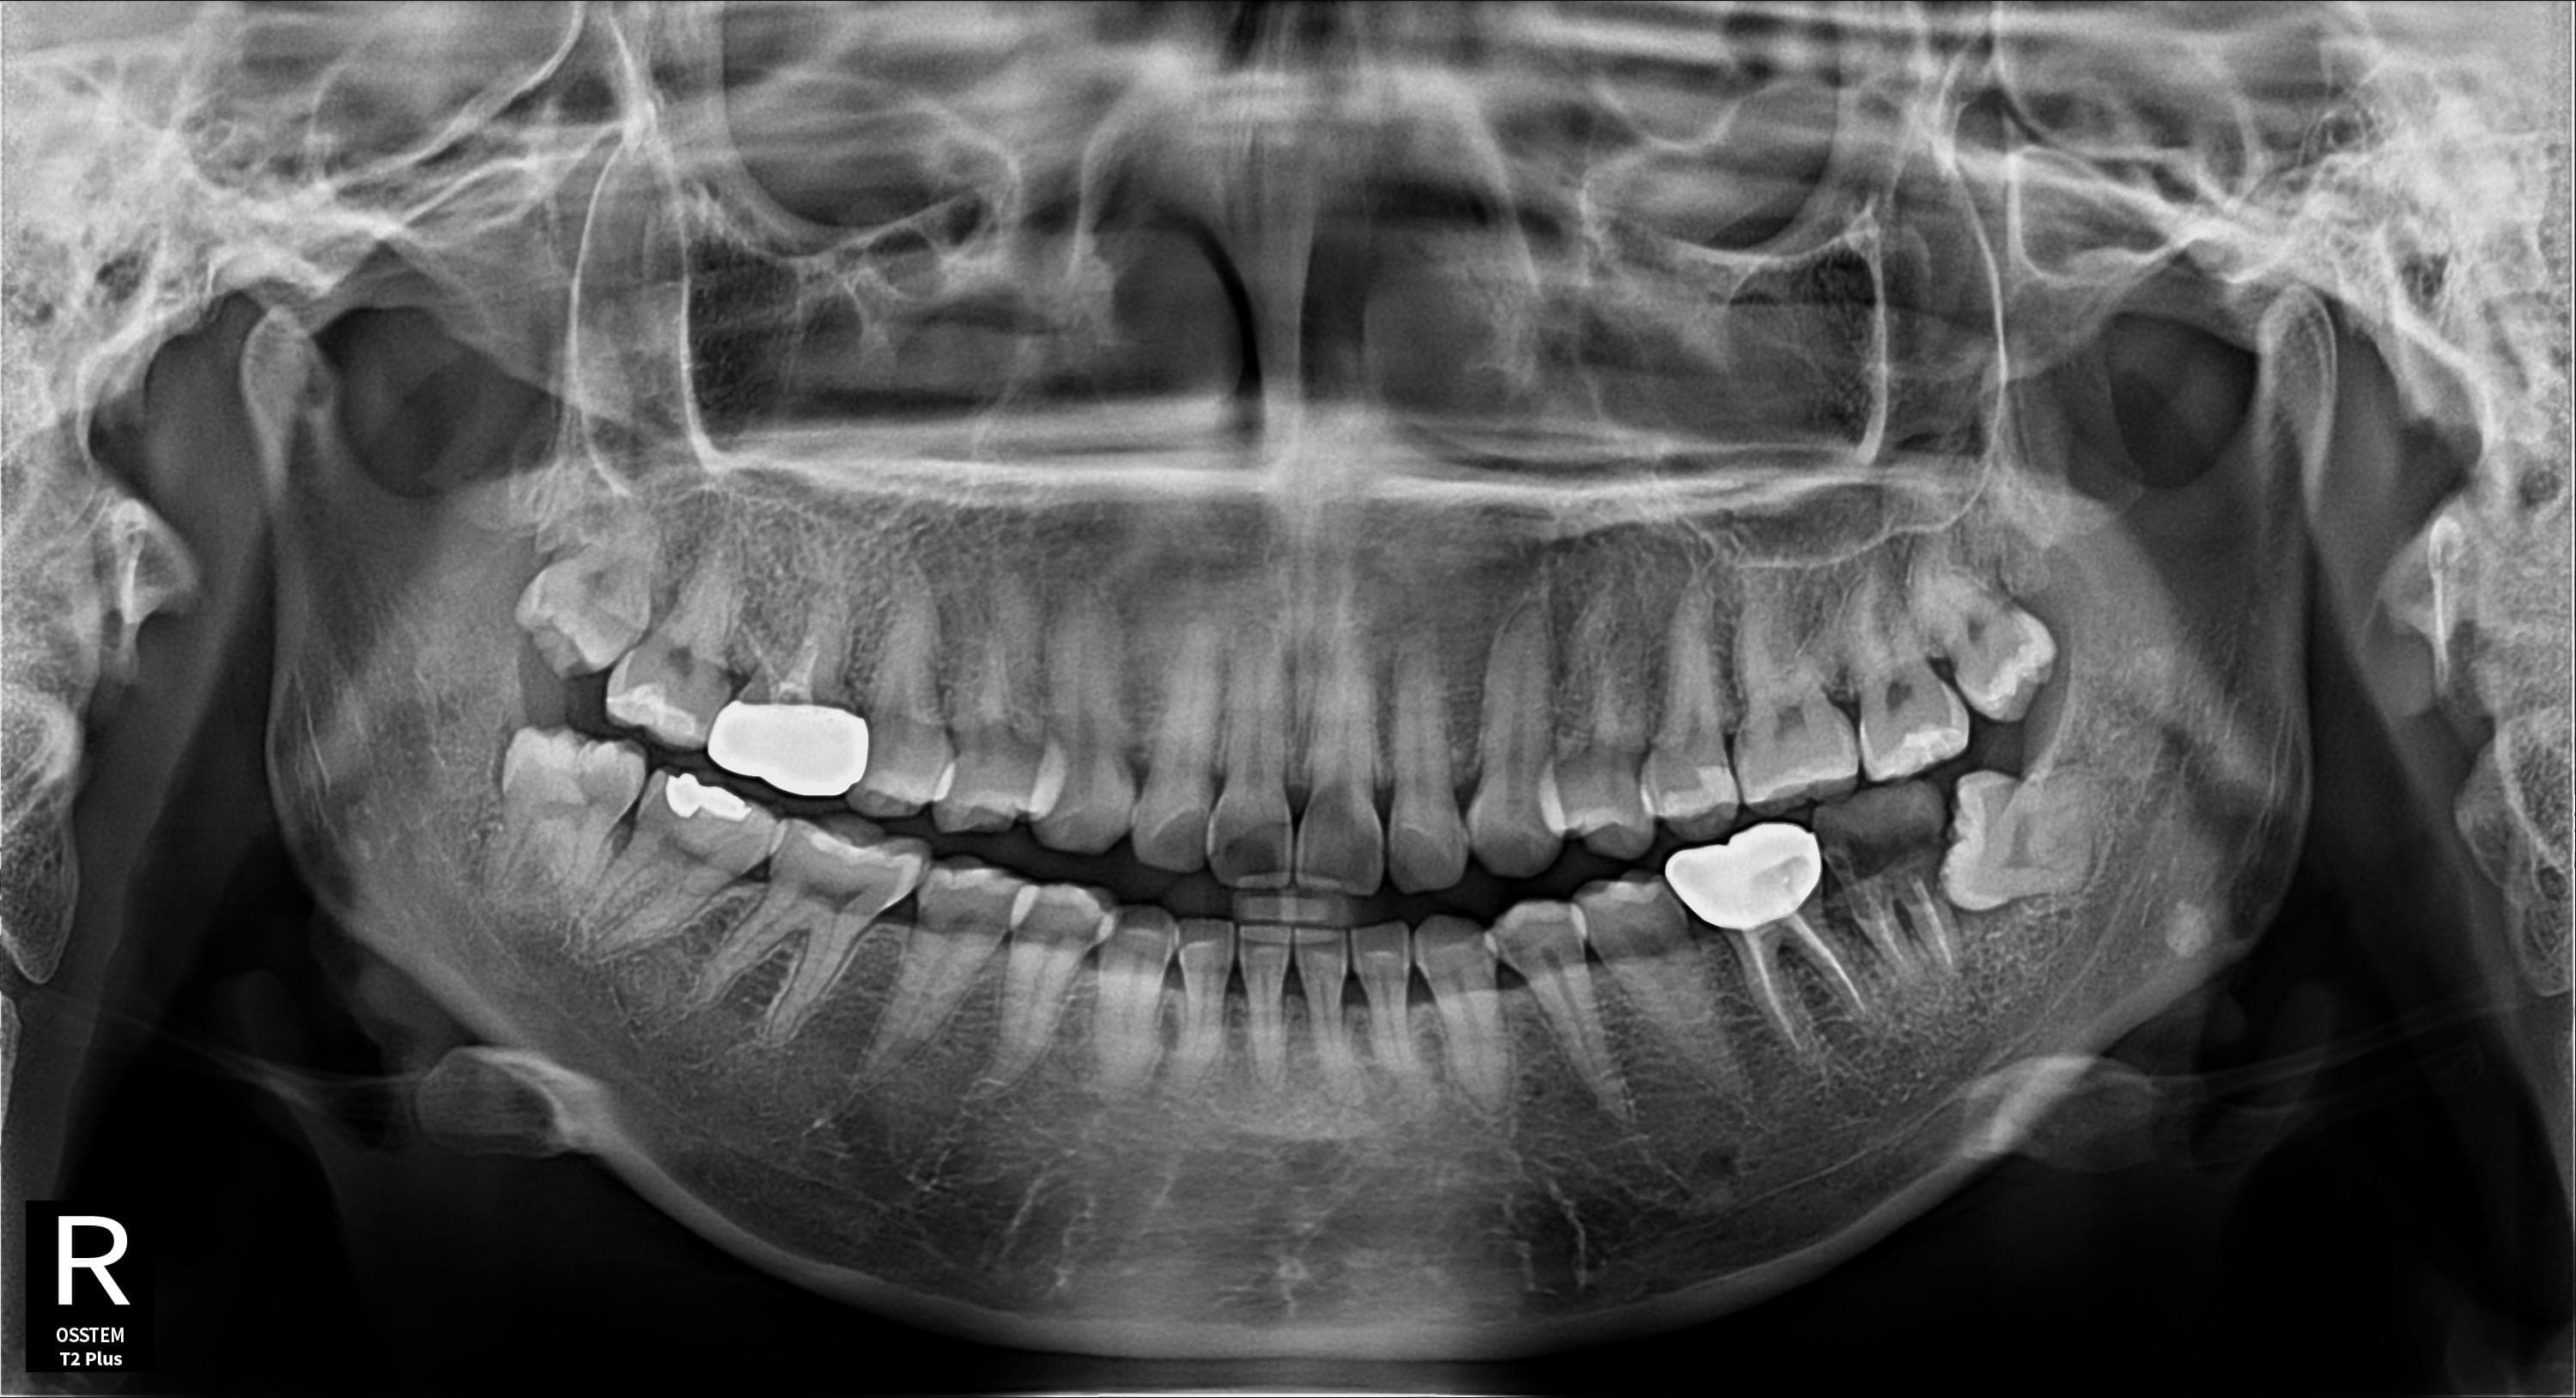

임플란트 + 사랑니 동시 시술

임플란트 식립과 사랑니 발치를 한번에

Before

After

임플란트 식립과 사랑니 발치를 동시에 진행하여 내원 횟수 최소화